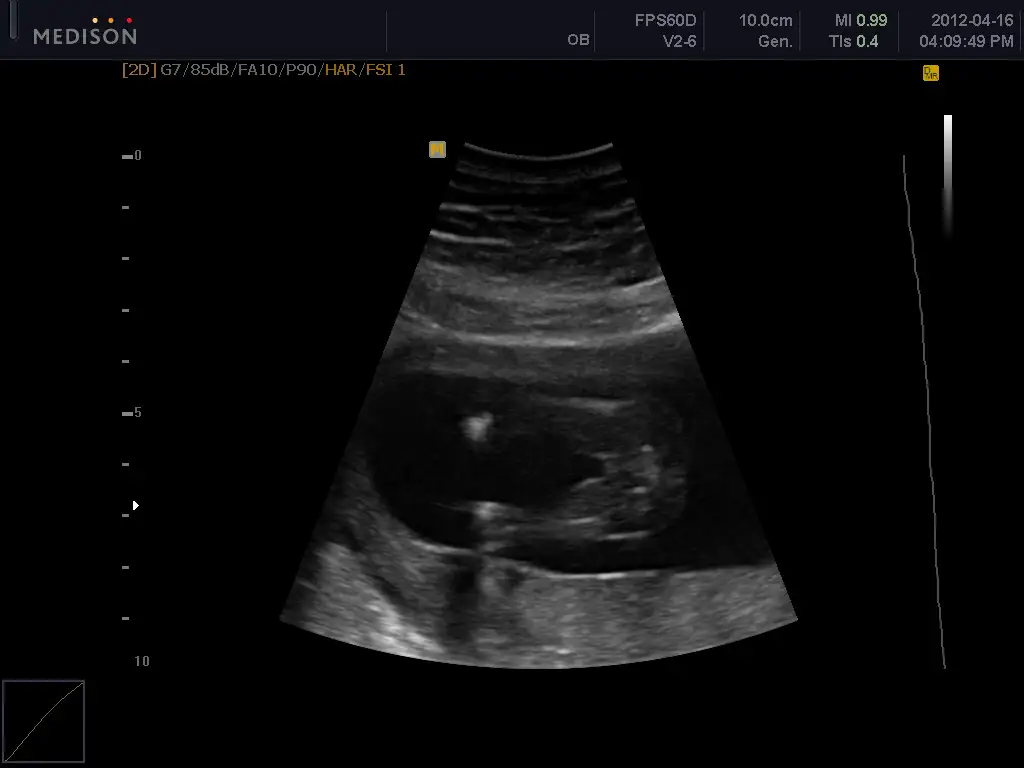

bende bugün bebeğimi ayrıntılı ultrason için 4 boyutluda görmey gititim çok belli yüzü

boydan veremem artık 5 ay bitti boy alınmıyor dedi

seninde son boydan dotoların :) bundan sonra profilden yüzden veriyorlar

bu arada bebekelr lastik gibiymiş doktor bebğimin ayağının alnında olduğunu söyledi :53:

ama ssaolsun bak bura ayak demedi sadece söyled, ben ekrandan baktım ama anlamadım

buda benim kzıım